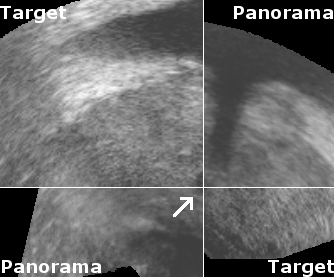

To measure reproducibility and registration success, 10 registrations were carried out for each volume pair from slightly perturbated start points by adding noise of 2mm and 2°. This yielded 10 transformations Tisubscript𝑇𝑖T_{i} that approximate the unknown rigid transformation between the prostate in both volumes. The average transformation T¯¯𝑇\overline{T} of the Tisubscript𝑇𝑖T_{i} was computed with the method presented in [9]. The euclidean distance error ϵEi=TiCT¯Csuperscriptsubscriptitalic-ϵ𝐸𝑖normsubscript𝑇𝑖𝐶¯𝑇𝐶\epsilon_{E}^{i}=||T_{i}\cdot C-\overline{T}\cdot C||, with C𝐶C being the image center, and the angular error ϵAisuperscriptsubscriptitalic-ϵ𝐴𝑖\epsilon_{A}^{i}, which corresponds to the rotation angle of Ti1T¯superscriptsubscript𝑇𝑖1¯𝑇T_{i}^{-1}\cdot\overline{T}, were used to compute the root mean square (r.m.s.) errors ϵEsubscriptitalic-ϵ𝐸\epsilon_{E} and ϵAsubscriptitalic-ϵ𝐴\epsilon_{A}. A registration was considered successful if ϵE<2.0subscriptitalic-ϵ𝐸2.0\epsilon_{E}<2.0mm and ϵA<5subscriptitalic-ϵ𝐴5\epsilon_{A}<5 degrees, and if the result T¯¯𝑇\overline{T} was visually satisfactory when superimposing both volumes in a composite image (See Fig. 2).

Reconstruction accuracy evaluation was more difficult to implement since there is no straight-forward gold standard. In some images, the needle trajectories from previous biopsies were still visible. In these cases, the trajectories were manually segmented, and the angular error between corresponding needle trajectories were used to evaluate rotational accuracy. Also, some patients had significant and clearly visible calcifications inside the prostate. The distances between segmented calcifications were used to determine the translational accuracy. Tab. 1 and Fig. 2 show the results of the evaluations.

Figure 2: Registration accuracy: (a) shows the target image, and (b) the aligned panorama image. In (c) both volumes are superimposed to illustrate registration accuracy for the urethra (arrow), and (d) illustrates the registration accuracy in the upper gland.